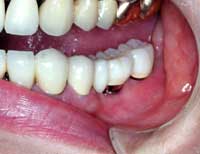

| Before | After |